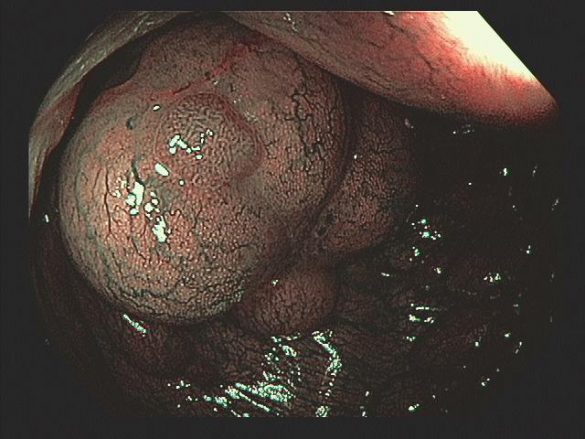

A PI pode afetar o intestino delgado, cólon ou ambos. Os cistos podem estar confinados à mucosa, submucosa ou subserosa, ou envolver todas as três camadas. Cistos subserosos são mais comumente vistos na pneumatose do intestino delgado, enquanto os cistos submucosos são mais comumente vistos na pneumatose cólica (como no caso em questão).

A PI pode ser descoberta incidentalmente na colonoscopia e deve-se prosseguir a investigação com ultrassonografia endoscópica. Cistos variam em tamanho de alguns milímetros a vários centímetros. Os cistos da submucosa costumam ter uma aparência pálida ou azulada e, quando biopsiados, podem desinflar rapidamente com um chiado audível.